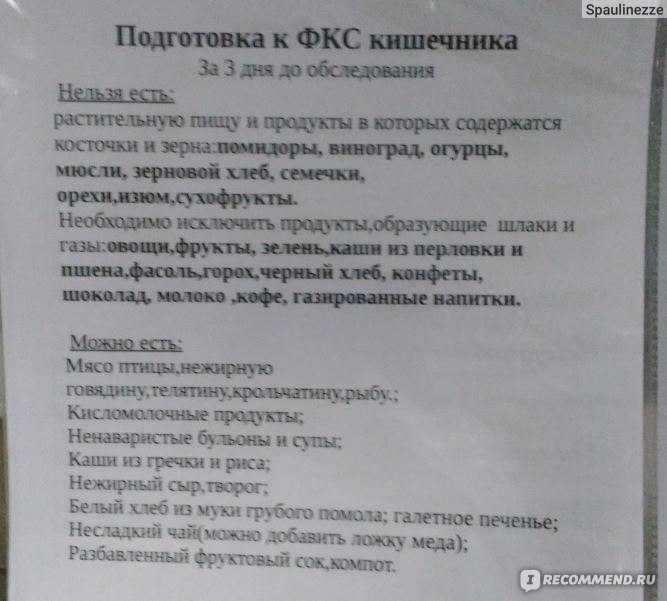

Подготовка к ирригоскопии: необходимые препараты